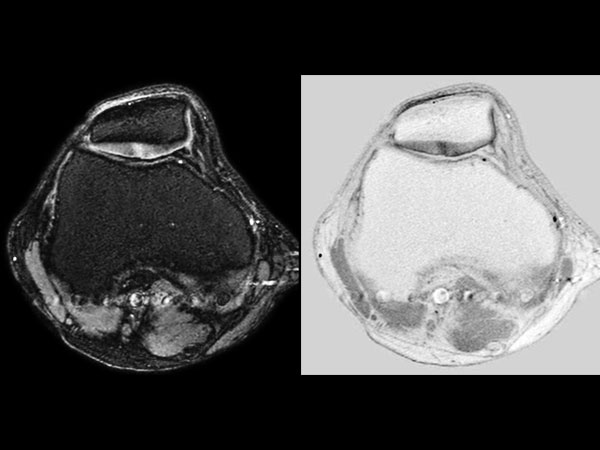

Knee Imaging with Cartilage Assessment

Middle aged board surfer presents with chronic knee pain. X-Ray shows no abnormalities. Follow-up MR examination requested.